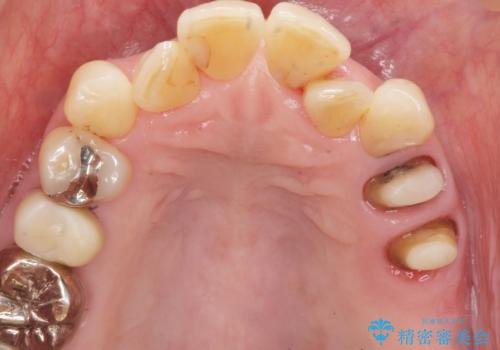

奥歯の違和感 再根管治療 40代女性

精査したところ、左上の大臼歯2本(左上67)が欠損しており、左上の小臼歯2本(左上45)は根が短く動揺があり根尖病変を認めました。

相談を重ねた上で小臼歯2本の再根管治療と連結補綴を行いました。

大臼歯がないため小臼歯に負担がかかりやすいことによるリスクを説明し、ご理解頂いた上で治療を行いました。

- ¥506,000 (再根管治療×2本、土台×2本、仮歯×2本、クラウン×2本) ※税込費用は治療当時の料金となります

クラウンの種類:オールセラミッククラウン スタンダード